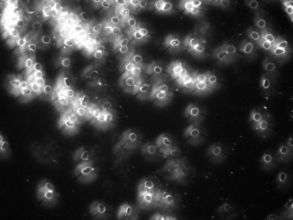

Levend Bloed Analyse

Levend bloed analyse is heel geschikt voor het herkennen van stofwisselings- en immuunsystemen. Door middel van het afnemen van een paar druppeltjes bloed via een vingerprikje, kunnen we heel veel aan jouw bloed aflezen. Er wordt gewerkt met een preparaat, waarin de witte en rode bloedcellen uren lang actief kunnen blijven. Vandaar dat er wordt gesproken van levend bloed.